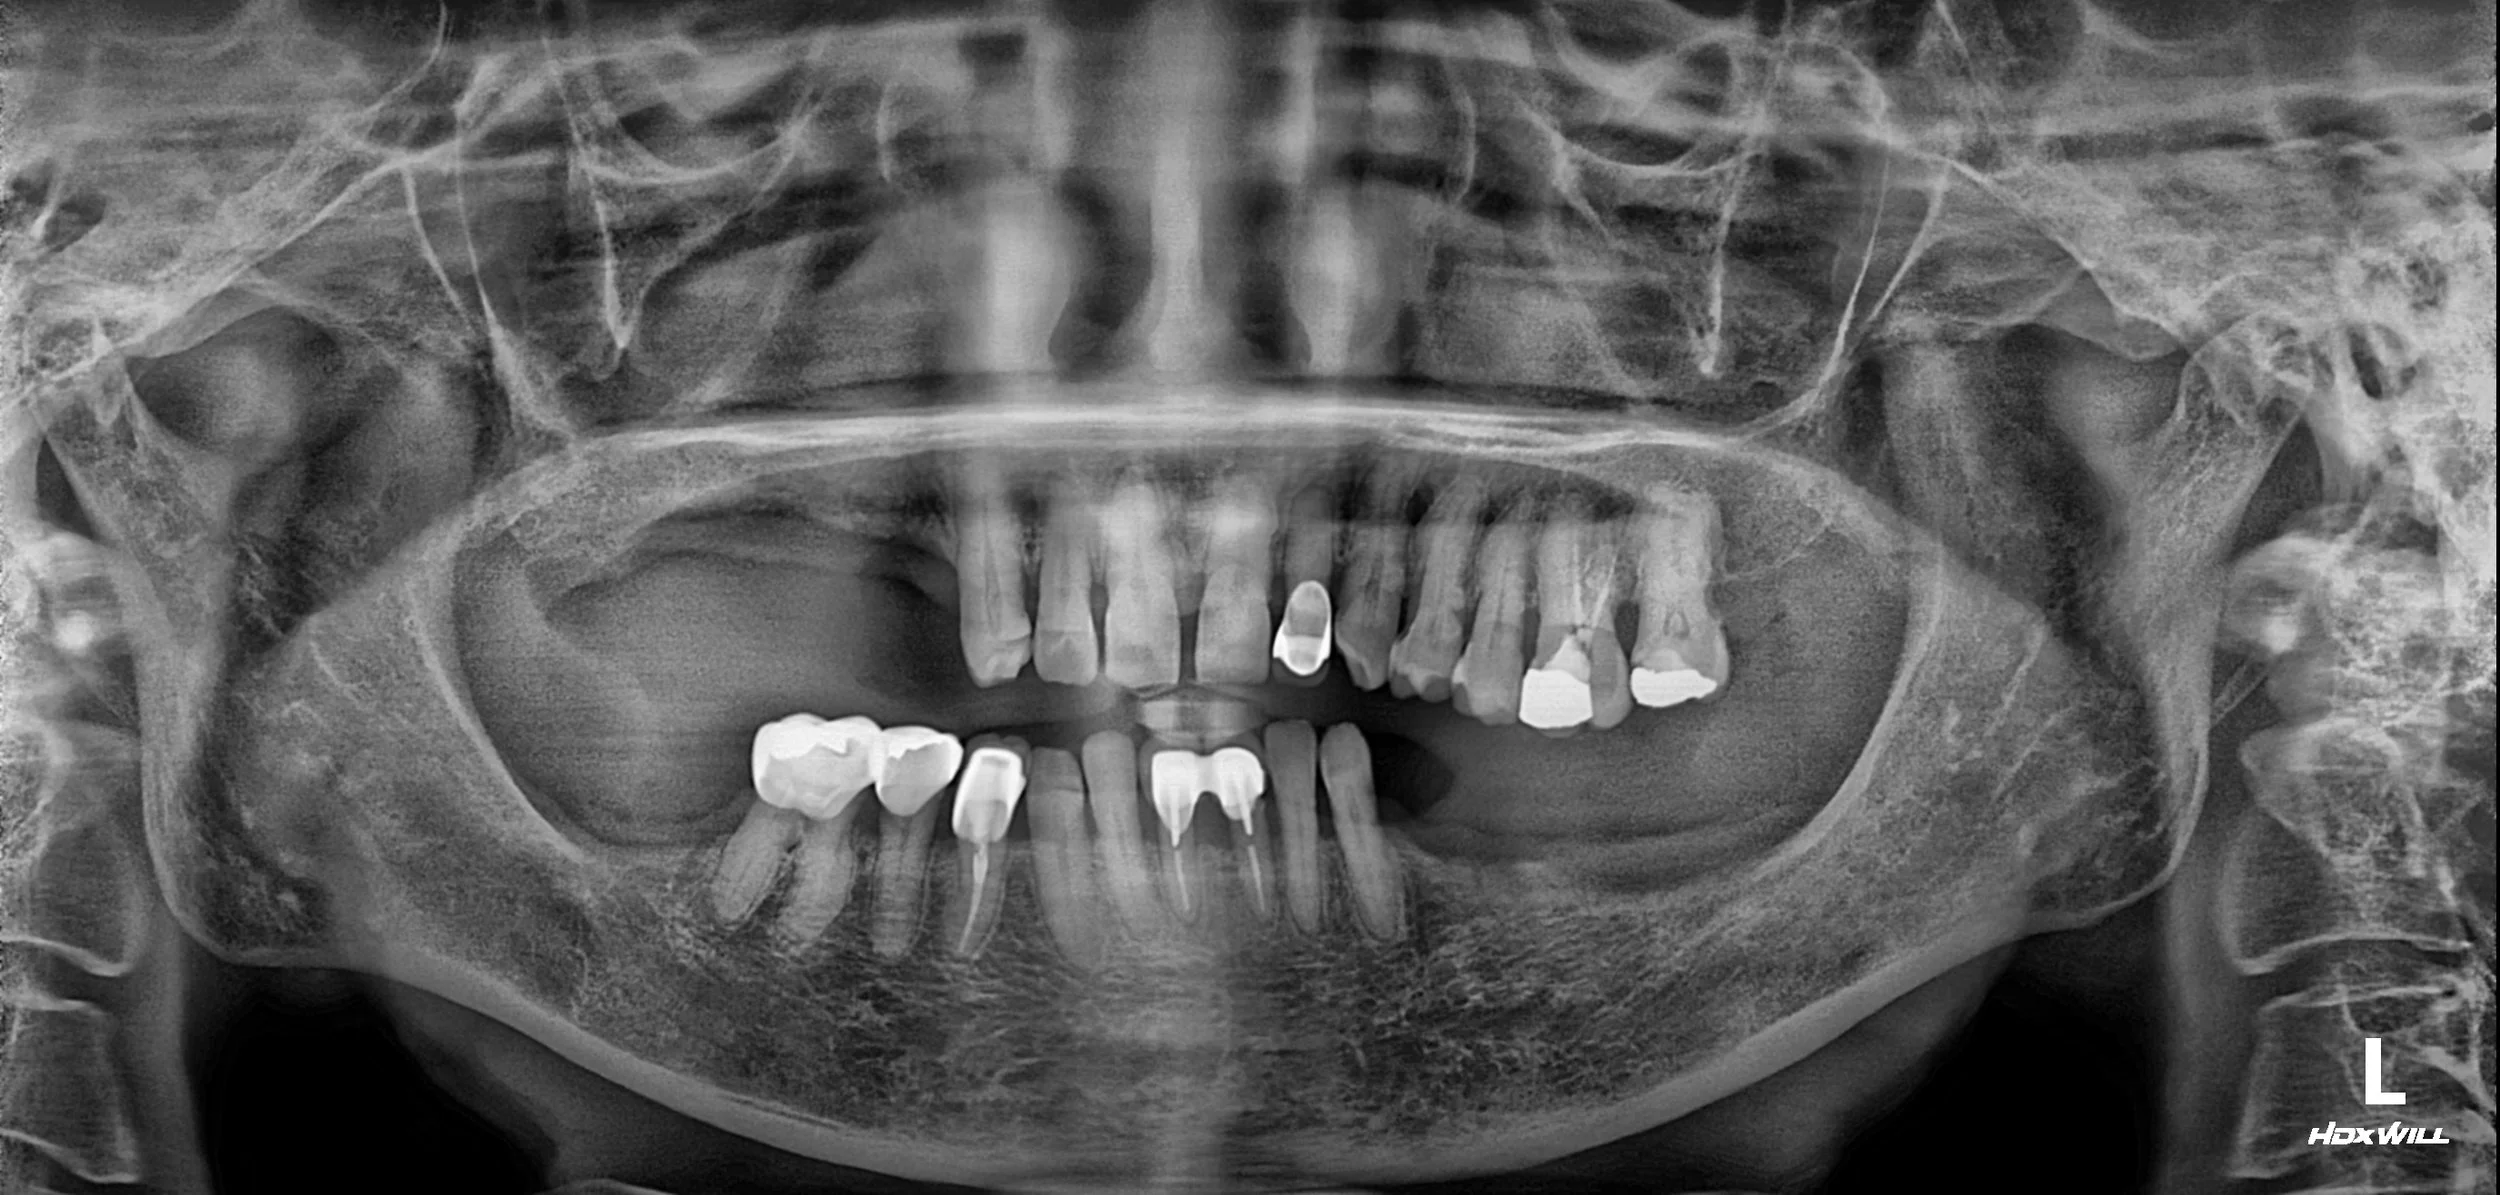

OPG - BEFORE